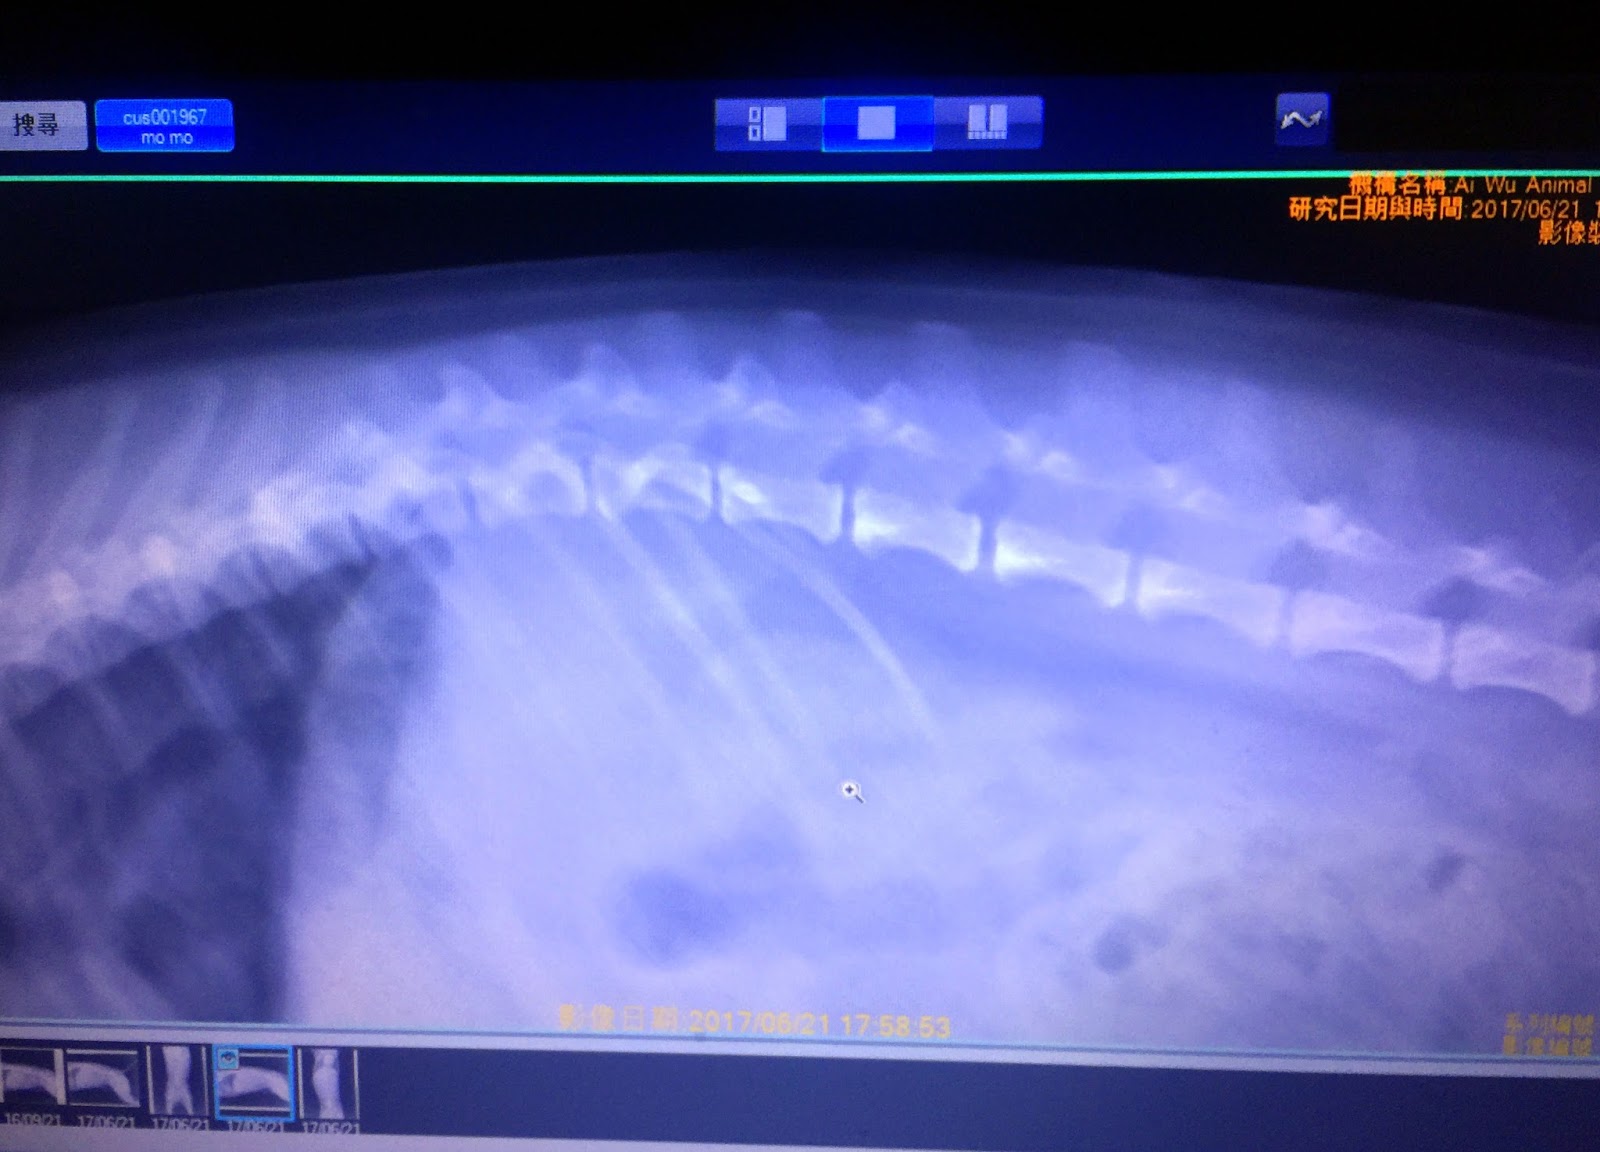

醫生講毛毛照

x

光片嗰陣都唔能夠做出指定動作拍攝,咁係正明毛毛腰部非常刺痛...

毛毛昨晚覆診⋯當時我建議醫生為毛毛做進一步檢查,照

光、抽血檢驗,等咗十五分鐘⋯有結果......

毛毛驗血數據所有指標正常,照片結果正實係毛毛腰椎突出問題復發,結果需然唔太意外⋯但足以令我全家都好憂心。

毛毛第一次受傷嗰陣醫生有講過呢種病會經常復發,但今次嘅過程令我震驚⋯由毛毛只係唔願意步行...兩三日間惡化到便便、尿尿動作都有困難,我想咗好耐都唔知毛毛喺邊度、幾時、唔知點樣受傷⋯防不勝防,家人都唔知點樣針對呢種病喺毛毛身上再度出現⋯感到無奈,可怕。